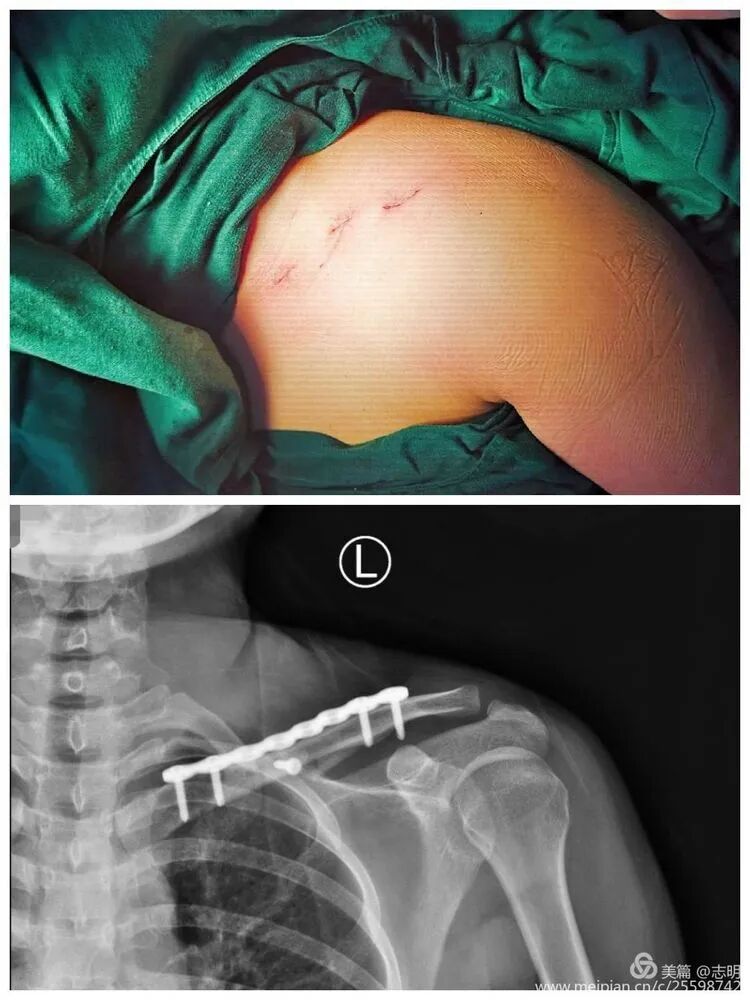

(Clinical image of small, well-healed MIPO incisions).(Another clinical view of minimal scarring).(Close-up of a small post-operative incision).(Clinical view of small post-operative incisions).(Clinical image demonstrating good range of motion post-operatively).

(This image shows a percutaneous tool, possibly for tunneling or reduction assistance).

(Post-fixation X-ray).(Healed fracture X-ray).(Another post-fixation X-ray).